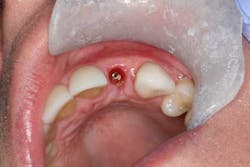

All patients are examined within two weeks of any surgery. Follow-ups then continue periodically (four to six weeks postsurgery) until the site is completely healed and patient is asymptomatic. If the treatment plan calls for tooth extraction and healing prior to implant placement, we schedule a “preoperative” appointment approximately three months after tooth extraction to evaluate hard and soft tissue contours, review the implant procedure and answer any questions, collect payment, and schedule for the implant surgery. Coordination with the restorative dentist is also done at this time if needed for surgical guides, etc. Following implant placement, the patient is seen for regular follow up as mentioned previously. Implant treatment plans often call for a waiting period after implant placement, prior to restoration. When the implant is suspected to be ready for loading, the patient is quickly seen for a “prerestorative check.” If an uncovery is needed to remove the cover screw and place a healing abutment, it is done two weeks prior the prerestorative check. During this visit, I evaluate proper gingival healing and soft tissue contours, take a periapical radiograph to check for any crestal bone loss, and ensure the implant is healed and ready for restoration. This appointment is also a method we use to follow up with our implant patients and insure they follow through with the restorative phase.Excellent soft tissue contours noted during prerestorative check.